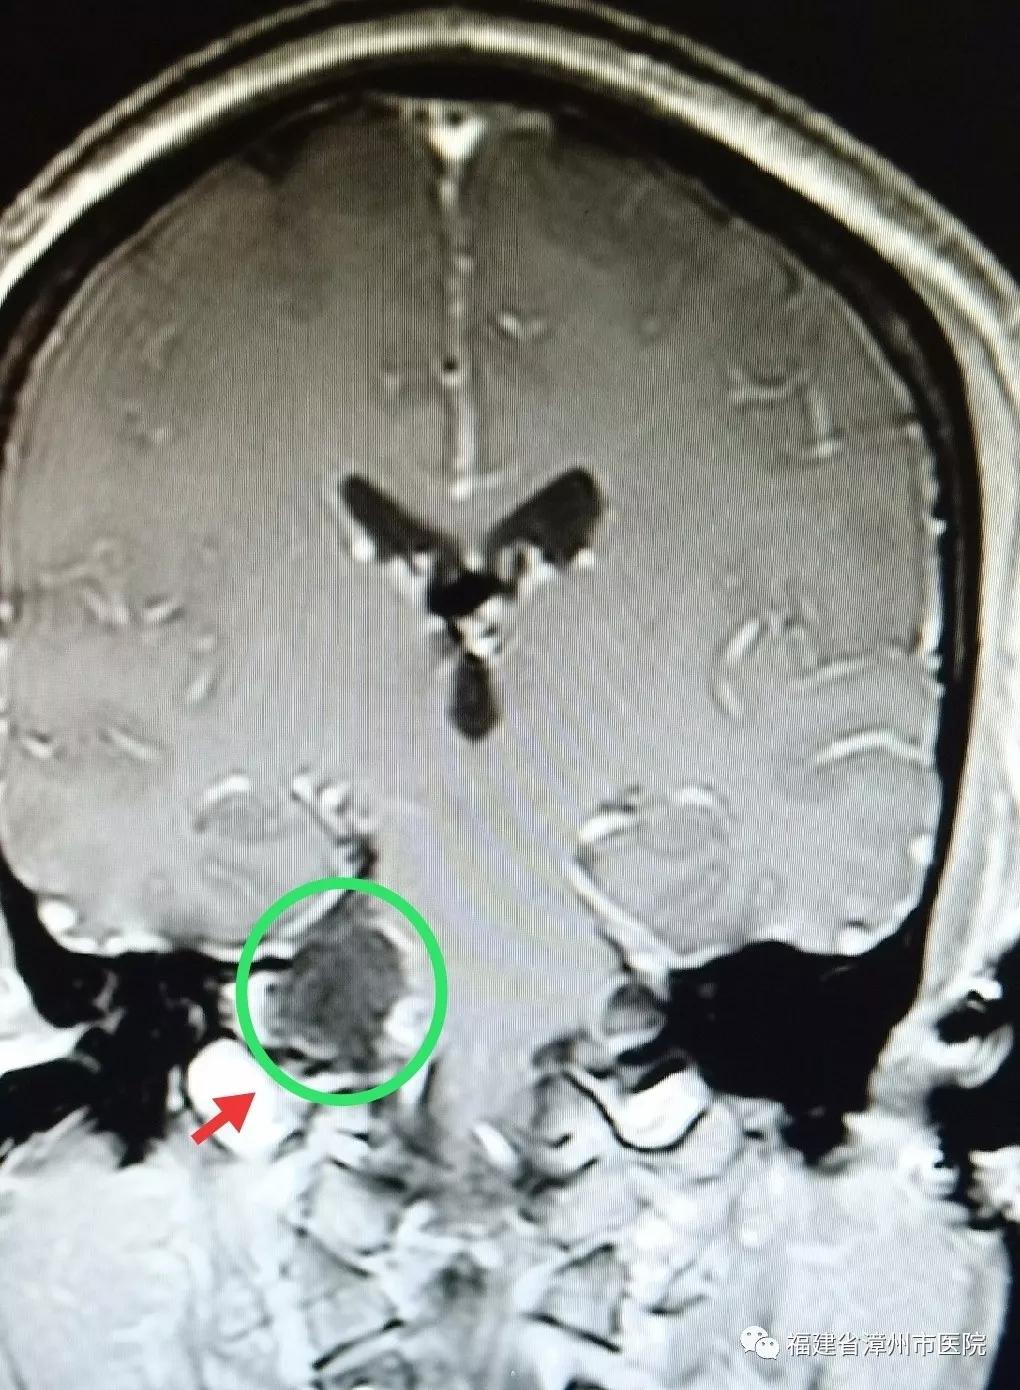

术前(肿瘤)

不久前到漳州市医院神经外科接受了颅内肿瘤切除手术的陈先生就是这种情况。陈先生今年52岁,由于做秘书工作,每天要接听数十个电话,工作压力大,情绪高度紧张。最近,打电话时他总听不清对方讲话,右边耳朵像有蜜蜂在飞,发出嗡嗡的声音。陈先生以为是手机信号不好,更换了手机,依然不奏效。有一次,他无意改用左耳听电话,感觉音质清楚了很多,这才意识到可能是自己耳朵出了问题。陈先生来到漳州市医院检查听力,我告诉他右侧听力明显下降,做磁共振检查后发现颅内有一个直径约5厘米的肿瘤,并且已经严重压迫脑干,并引起脑积水。我询问病史得知,原来4年前陈先生就感觉右耳听力下降,感觉有些耳背,他以为是工作压力大所致,一直没在意。

陈先生因为忽视,延误了最佳治疗时机。当检查发现时,肿瘤已经有5厘米大小,伴有多颅神经损害如轻微面瘫、面部麻木等症状及脑积水存在,脑干重度压迫移位。经过显微神经外科手术,目前已切除肿瘤,顺利出院。